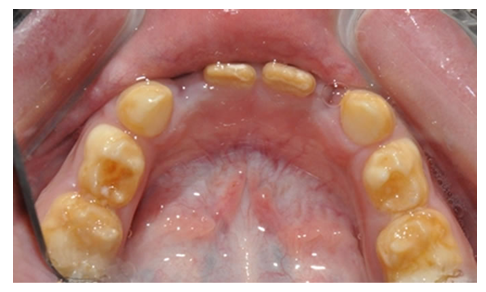

Vrlo je važno da se razlikuje karijes od razvojnog defekta. Karijes se pojavljuje kao bela mrlja na prethodno normalnoj gleđi i to pre svega uz ivicu desni. Rezvojni defekat je uglavnom na drugim površinama, gde se karijes ne javlja. (Slika 4. i 5)

Slika 4. Karijes se uvek javlja uz desni i počinje kao bela mrlja(desno), razvojni defekti(hipoplazija) su češće na drugim delovima zuba(levo)

Karijes kod beba brzo napreduje i razara celu površinu zuba, pa ponekada može da podseća i na razvojne defekte.(Slika 5.)

Slika 5. Karijes kod beba brzo napreduje i podseća na razvojni defekt.